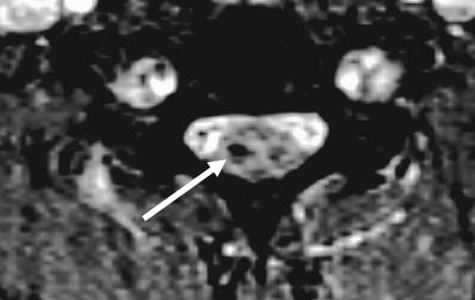

(Справа) На аксиальном GRE МР-И у пациента с флексионной травмой шейного отдела позвоночника видно массивное паренхиматозное кровоизлияние в центральной части спинного мозга, характеризующееся в этом режиме низкой интенсивностью сигнала. Такая картина является плохим прогностическим признаком возможности полноценного функционального восстановления. (Слева) Рентгенограмма в боковой проекции: расширение промежутка между остистыми отростками С6 и С7. Нижний суставной отросток С6 находится впереди верхнего суставного отростка С7.

МРТ шейного отдела позвоночника. Аксиальная Т2-взвешенная МРТ. Кровоизлияние в спинной мозг.